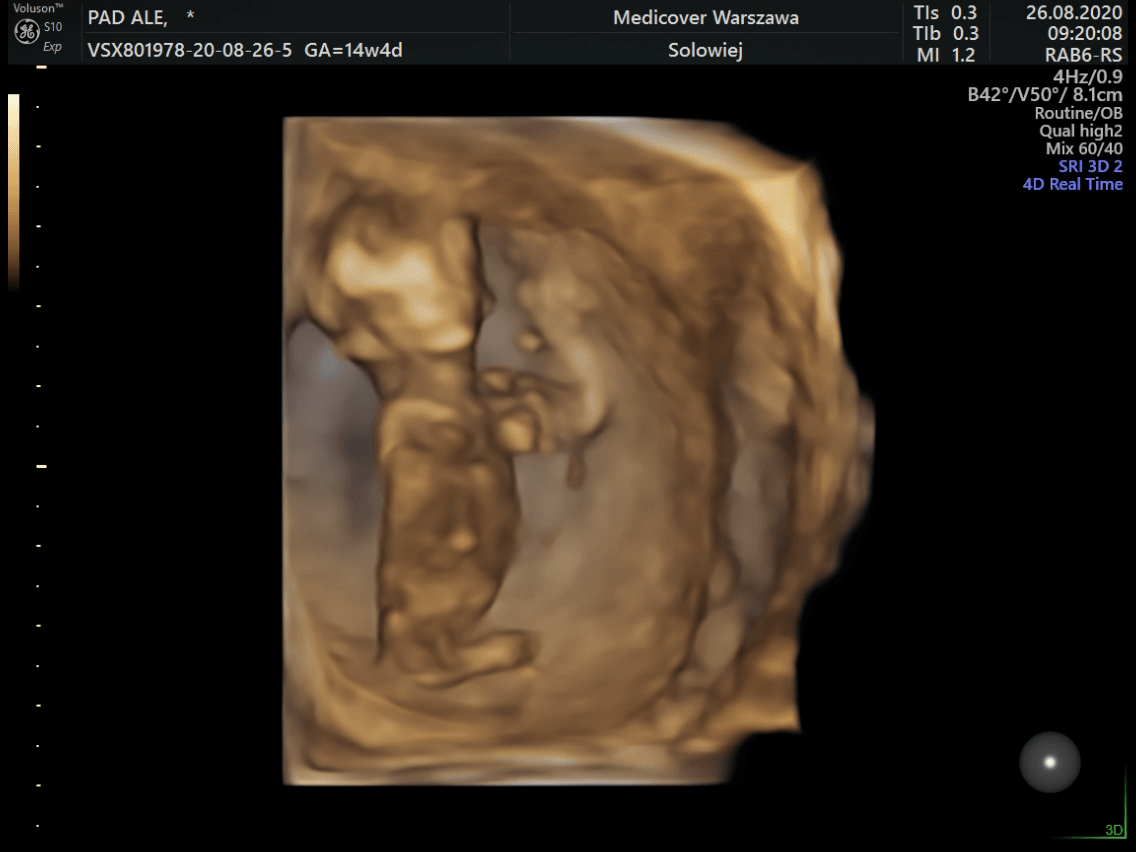

Ojaaa ale super. Nam machał :D mam nagranie i tak się przywitał ze wszystkimi ciociami i wujkami :)

Załączniki

• received_1487799851408637.png

received_1487799851408637.png

170,7 KB · Wyświetleń: 114